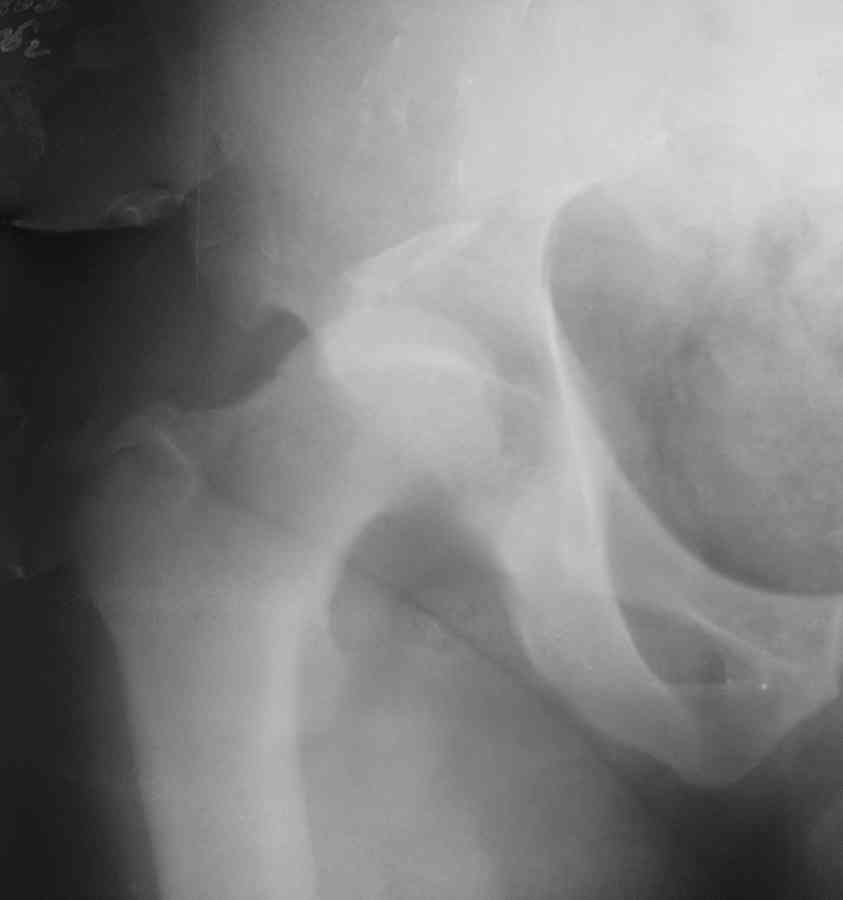

Еще одно наблюдение, неправильно сросшийся перелом заднего отдела ВВ с ввихом головки бедра 16-и летней давности.

С уважением, Р.Тихилов

Большое спасибо за ответ, примеры впечатляют, особенно случай с переломом задней колонны. Интересно отличаются ли у Вас доступ при значительных проблемах в задних отделах от стандартного, всегда ли хватает головки или берете кость из других мест, отличается ли послеоперационное ведение у таких больных (когда нагрузка?).